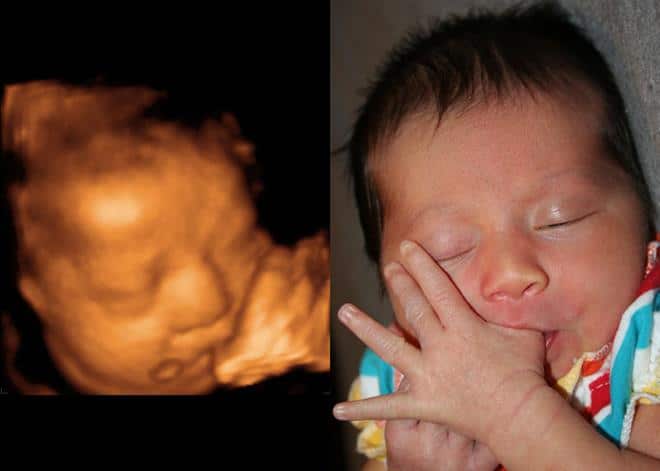

Mas será que o bebê realmente ficará como mostra o ultrassom 3D? Veja a seguir 23 fotografias do antes e o depois do mesmo bebê para conferir:

A ultrassom 3D é capaz de mostrar rostinho do bebê com detalhes. Foto: Firstimpression3dJá existem as ultrassonografia em 4D, que mostram as imagens em movimento. Foto: Firstimpression3dOs ultrassons 3D é capaz de mostrar até o bocejo do bebê. Foto: Firstimpression3dO ultra 3D também detecta algumas anomalias do bebê. Foto: Firstimpression3dCom essa ultrassom é capaz de perceber se o bebê parecerá com a mãe ou o pai. Foto: Firstimpression3dAlgumas posições que o bebê faz na barriga, viram costume após o nascimento. Foto: firstimpression3dOs ultrassons 3D e 4D são feitos entre as semanas 26 e 29. Foto: GunbaseOs exames 3D podem custar cerca de 200 a 300 reais. Foto: KolyokkuponNão é necessário nenhum preparo especial para realizar o ultra 3D. Foto: GunsbaseOs resultados de exames 3D são realmente impressionantes! Foto: 3dand4dVale a pena fazer o antes e depois do ultrassom 3D do seu bebê. Foto: ImgkidÉ emociante para a mãmae poder conhecer o rostinho do bebê antes do nascimento. Foto: ImgbuddyHá casos que o bebê pode ter algumas mudanças em relação ao ultrassom 3D. Foto: ImgbuddyAté o sorrisinho do bebê pode aparecer na ultrassonografia 3D. Foto: GurugossiperMuitas mamães se impressionam com a semelhança do resultado do exame com o bebê nascido. Foto: 3dand4dA boca e o nariz são os mais perceptíveis nas ultrassonografias 3D. Foto: The BumpComo é possível perceber na ultra 3D, a pele do bebê já está completamente formada. Foto: InfantSee4DA ultrassonografia 3D são como fotos. Para ver o bebê em terceira dimensão em movimento, terá que fazer a ultra em 4D. Foto: 3DBabyBumpA qualidade do exame 3D dependerá da posição do bebê na hora da ultrassonografia. Foto: Southport VisiterApesar do rostinho está praticamente formado, o bebê ainda não abre os olhinhos. Foto: Moms To Be UltrasoundAs ultrassonografias em 3D não são obrigatórias, é um exame opcional. Foto: BabysitioApesar do valor, vale a pena investir na ultrassom em 3D. O custo benefício é gratificante! Foto: InfantSee4D